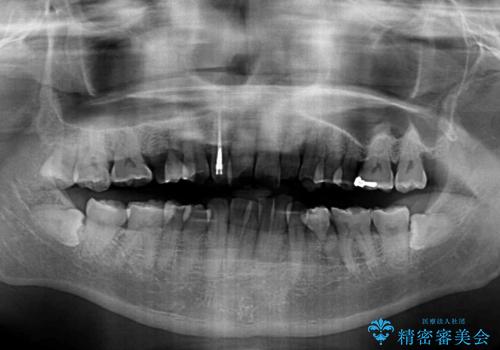

全額的にデコボコが強いため、上下左右の小臼歯計4歯を抜歯し、ワイヤー装置による矯正治療を行うこととしました。

抜歯する歯の一部をセオリーである第一小臼歯ではなく、第二小臼歯にすることで、骨格的なずれをカバーするように計画しました。

小臼歯の抜歯する部位を選択したことで、安定した咬み合わせとなりましたが、第二小臼歯を抜歯した部分はスペースを閉じるのに長い期間を要しました。